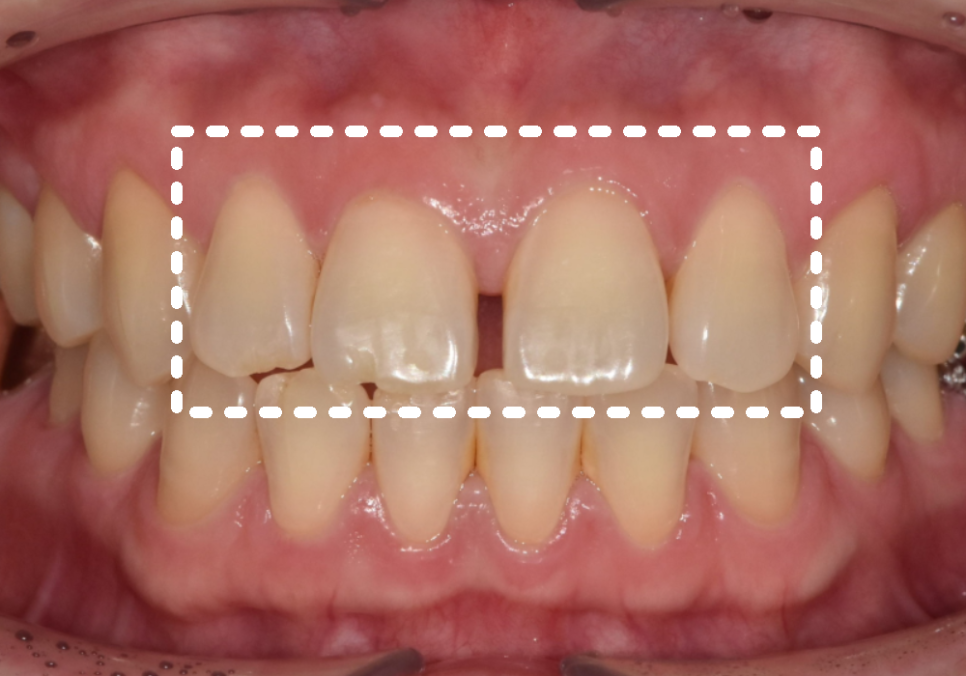

라미네이트를 통해

앞니 4개의 균형을 맞추고 나니,

단 며칠 만에 인상이 훨씬 단정해지셨습니다.

앞니 4개는 라미네이트로 빠르게 개선하고,

어금니는 즉시 임플란트를

진행하기로 결정했답니다.